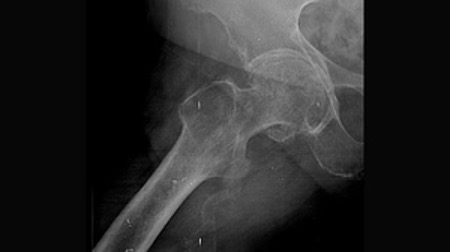

所有参与者均为 50 岁及以上年龄组,且在至少 3 个月内持续遭受严重的髋部疼痛,同时影像学检查显示有股骨或髋臼骨赘形成以及关节间隙变窄的情况。